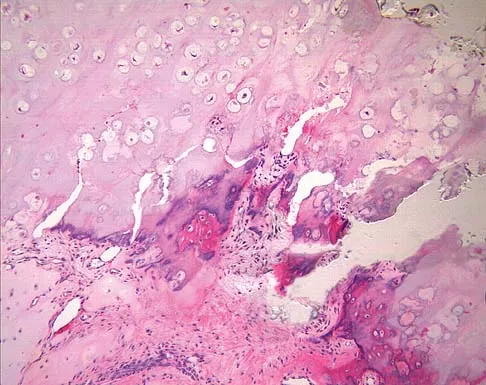

A 9-year-old boy has a painless enlarged mass on the dorsum of his hand. Figures 14a through 14d show the clinical photograph, radiographs, and biopsy specimen. What is the most likely diagnosis?

Explanation

Multiple hereditary exostosis and enchondroma commonly present as multiple lesions in the hand. Multiple hereditary exostosis consists of cartilage capped bony exostoses arising from the metaphyseal end of rapidly growing bones. Osteosarcoma and chondrosarcoma rarely appear as multiple lesions. Fracture callus can exhibit enchondral ossification that is usually circumferential, but the radiographic findings are not consistent with fracture. Porter DE, Emerton ME, Villanueva-Lopez F, Simpson AH: Clinical and radiographic analysis of osteochondromas and growth disturbance in hereditary multiple exostoses. J Pediatr Orthop 2000;20:246-250.